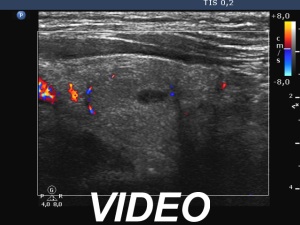

Ultrasonography: Both lobes had hypoechoic areas which showed ill-defined borders. The echogenicity index was around 50%. The hypoechoic areas were avascular.

Ultrasonography: Both the size of the nodule and the extent of hypoechoic areas have decreased. An isoechoic nodule has appeared which was obscured by hypoechogenicity in the previous study. The vascularity was still very scanty.

Ultrasonography: The dorsal part of the right lobe remained hypoechoic. The nodule in the left lobe has increased in size and presented halo and signs of perinodular vascularity.